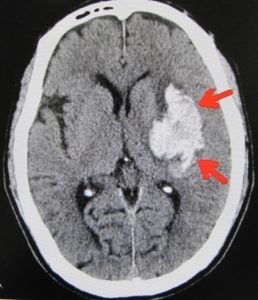

短時間で一度に広範囲の撮影が可能で、多くの情報を得られることがCT検査の大きな特徴です。CT検査は特に、脳出血、肺炎や肺がん、骨折、腹部疾患の診断に有用です。また、骨折部位を立体的に確認できる3D画像作成にも活用され、治療方針の決定や手術計画にも役立てられています。

脳出血